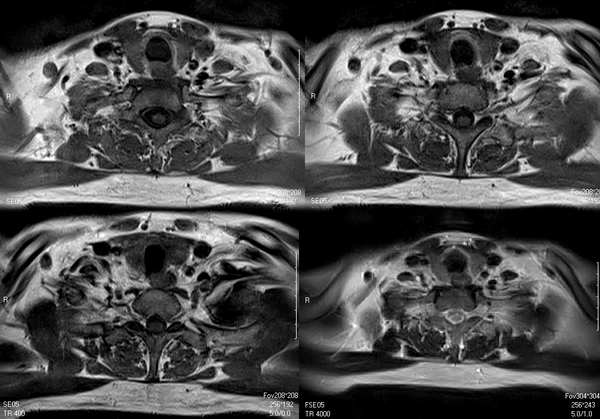

标题: MRI0436:食管病变或甲状旁腺瘤?还是神经源性肿瘤?

男,40岁,体检时发现病变,食管病变或甲状旁腺瘤?还是神经源性肿瘤?

横轴位没看到哪有瘤子